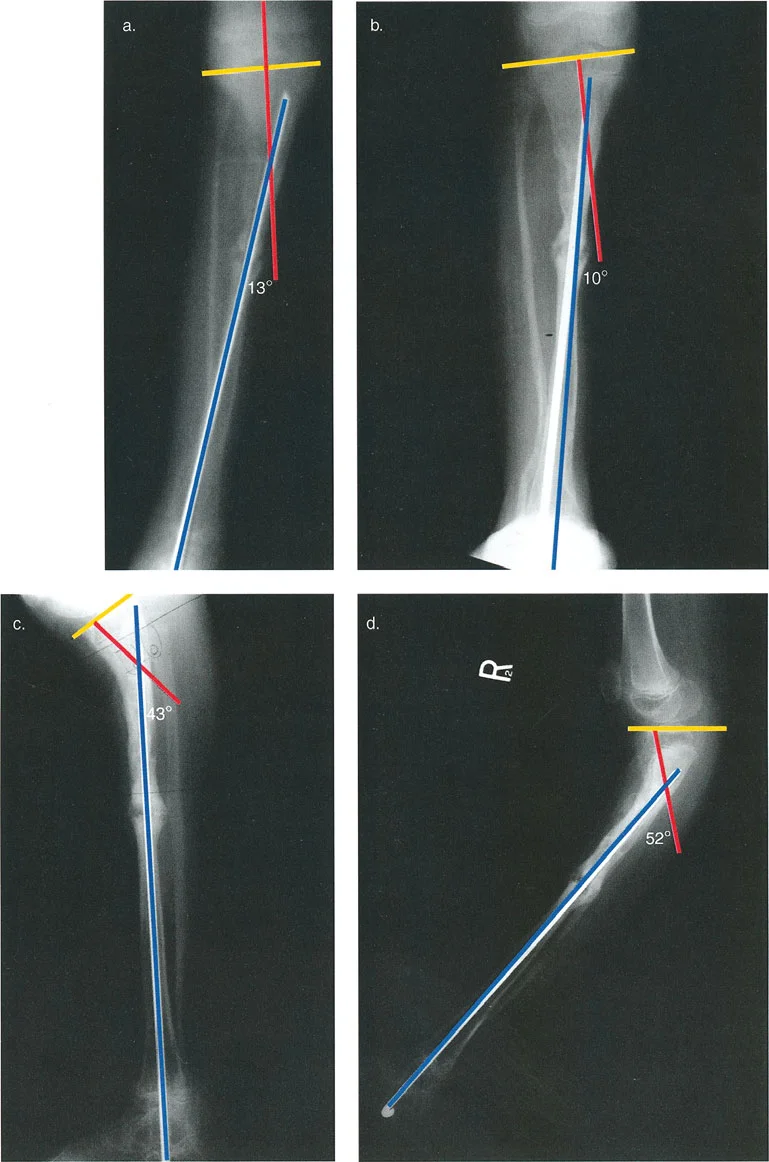

التصوير الإشعاعي المتقدم:

- الأشعة السينية الطويلة (Full-Length Standing X-rays): هذه الأشعة ضرورية لتقييم المحور الميكانيكي الكامل للطرف السفلي أثناء وقوف المريض وتحميل الوزن. تسمح هذه الصور بتحديد الانحرافات في زوايا المفاصل الرئيسية مثل:

- الزاوية الفخذية البعيدة الجانبية الميكانيكية (mLDFA): الطبيعي حوالي 87 درجة.

- الزاوية الظنبوبية القريبة الإنسية (MPTA): الطبيعي حوالي 87 درجة.

- الزاوية الظنبوبية البعيدة الجانبية (LDTA): الطبيعي حوالي 89 درجة.

- عندما تكون إحدى هذه الزوايا غير طبيعية، فإنها تشير إلى موقع التشوه (في الفخذ، الساق، أو داخل المفصل).

- الأشعة السينية الأمامية الخلفية والجانبية (AP and Lateral Radiographs): تُستخدم لتقييم التشوه في المستويين التاجي (التقوس للداخل أو الخارج) والسهمي (التقوس للأمام أو الخلف).

- التصوير المقطعي المحوسب (CT Scan): يُعد حاسمًا لتقييم التشوهات الدورانية (الالتواء) التي لا تظهر بوضوح في الأشعة السينية التقليدية، ولإجراء قياسات ثلاثية الأبعاد دقيقة للعظم.

- يعتمد تحليل التشوه بشكل كبير على زوايا توجيه المفاصل القياسية لتحديد ما إذا كان التشوه في عظم الفخذ، أو الساق، أو داخل المفصل نفسه. تشمل الزوايا الرئيسية:

- الزاوية الفخذية البعيدة الجانبية الميكانيكية (mLDFA): الطبيعي 87 درجة.

- الزاوية الظنبوبية القريبة الإنسية (MPTA): الطبيعي 87 درجة.

- الزاوية الظنبوبية البعيدة الجانبية (LDTA): الطبيعي 89 درجة.